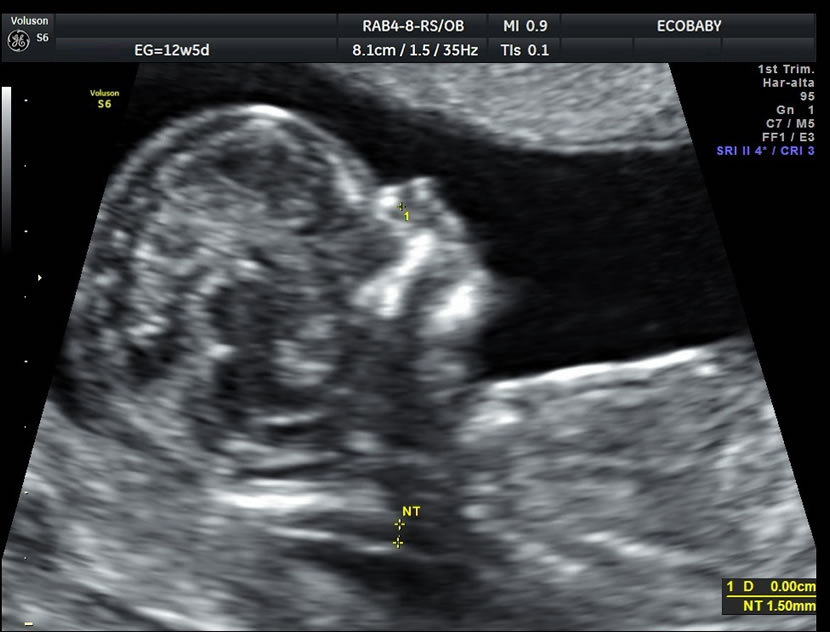

> Para medir el grosor de líquido detrás de la nuca del feto (translucencia nucal)